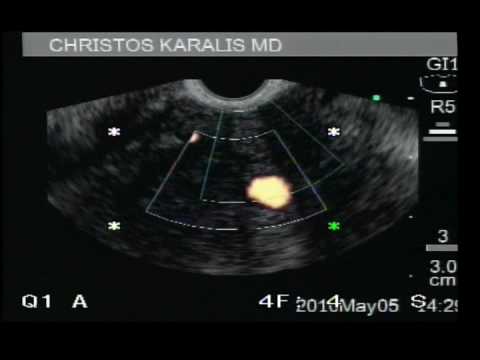

Rak Trzustki W Badaniu EUS - Stadium T4.

Poniższy materiał wideo przestawia raka trzustki (stadium T4) w badaniu EUS.

Przewlekłe Zapalenie Trzustki - Endoskopowa Ultrasonografia

Patologie trzustki mogą być diagnozowane przy użyciu endoskopowej ultrasonografii. Na poniższym materiale pokazano biopsję cienkoigłową miąższu trzustki - podejrzenie przewlekłego zapalenia lub procesu...

Zmiana W Trzustce - Endoskopowa Ultrasonografia

Patologie trzustki mogą być diagnozowane przy użyciu endoskopowej ultrasonografii. Na poniższym materiale pokazano biopsję cienkoigłową miąższu trzustki - podejrzenie przewlekłego zapalenia lub procesu...